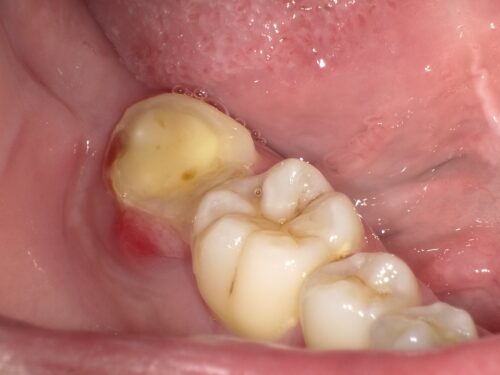

割れてしまった奥歯です。

歯が真ん中から割れており、痛みを生じていました。

レントゲン写真を見ると、以前根管治療を受けて失活歯(神経が死んでいる歯)となっていたことがわかりました。

赤い円で示しているところです。この歯が破折してしまいました。

割れた破片を取り除いた直後の状態です。

骨の中まで割れていたことが確認できます。このような深い破折の場合、通常は抜歯が必要となります。